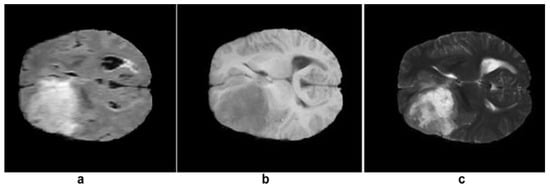

| T1 | T2 | Flair | |

|---|---|---|---|

| White Matter | Bright | Dark | Dark |

| Gray Matter | Gray | Dark | Dark |

| CSF | Dark | Bright | Dark |

| Tumor | Dark | Bright | Bright |